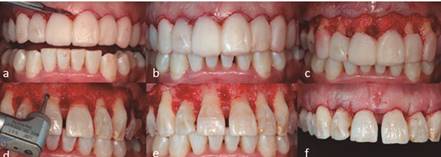

El 25 de agosto de 2016, día en que se realizó el procedimiento, la paciente firmó el consentimiento informado, declarando estar de acuerdo en la utilización de su caso para fines académicos. Se inició el alargamiento de corona con la anestesia del segundo premolar superior derecho al segundo premolar superior izquierdo con mepivacaína al 2% con epinefrina (1:100,000) (Septodont, México). Se colocó mock up proporcionado por el área de prótesis y se realizaron incisiones con hoja de bisturí 15C (Ribbel, Nueva Delhi) en base al mismo, el cual fue utilizado como guía para delimitar la zona a tratar (Figura 4a). Una vez delimitada la zona, se realizaron incisiones a bisel interno, haciendo los cortes de mesial a distal de cada diente. Enseguida se realizaron incisiones intrasurcales para obtener una banda de tejido gingival, que posteriormente sería retirada con curetas Gracey (Figura 4b). Posterior a esto, con legra Prichard se levantó colgajo de espesor total con el cual se obtuvo acceso al hueso alveolar, donde se pudo observar los márgenes discrepantes (Figura 4c). Se realizó ostectomía seguido de osteoplastía con pieza de mano de baja velocidad con fresa de bola de carburo #4, usando simultáneamente abundante irrigación con suero fisiológico y respetando las raíces (Figura 4d). Se midió la distancia desde el margen protésico hasta la nueva altura de cresta ósea para obtener una distancia de 3 mm. El hueso remanente en las raíces de los dientes se eliminó con cincel CTG-0 (Figura 4e). Una vez terminado, se suturó el colgajo con ácido poliglicólico 4-0 con puntos suspensorios (Atramat, México) (Figura 4f). Se le recetó a la paciente ibuprofeno de 600 mg uno cada 8 horas durante 3 días y enjuagues con gluconato de clorhexidina al 0.12% cada 12 horas por 15 días. Se le indicó mantener buena higiene, sin cepillar o hacer uso de aditamentos interproximales en la zona tratada.

A los siete días (1 septiembre) se realizó retiro de suturas, se observó clínicamente la zona tratada desinflamada, del mismo color de la mucosa adyacente y sin signos de infección (Figura 5a). A las tres semanas de la cirugía se prepararon los dientes y se colocaron los provisionales (Figura 5b) y a las cinco semanas (30 septiembre) se realizó un recontorneo gingival con ayuda de electrobisturí (Figura 6a). A las nueve semanas se observó una adecuada cicatrización y se procedió a hacer toma de impresión (Figura 6b). El 2 de febrero se colocó la restauración final, observando tejidos sanos y estéticos (Figura 7). Mediante el procedimiento quirúrgico se logró la corrección y restablecimiento de los márgenes gingivales según los requerimientos protésicos, se obtuvo además la longitud coronaria deseada en la planeación del diseño de sonrisa. La realización de recontorneo gingival con electrobisturí permitió crear cénits más armoniosos y ayudó a crear mayor simetría en los márgenes gingivales. La paciente expresó sentirse contenta con los resultados finales tanto de la cirugía como de la colocación de las carillas.